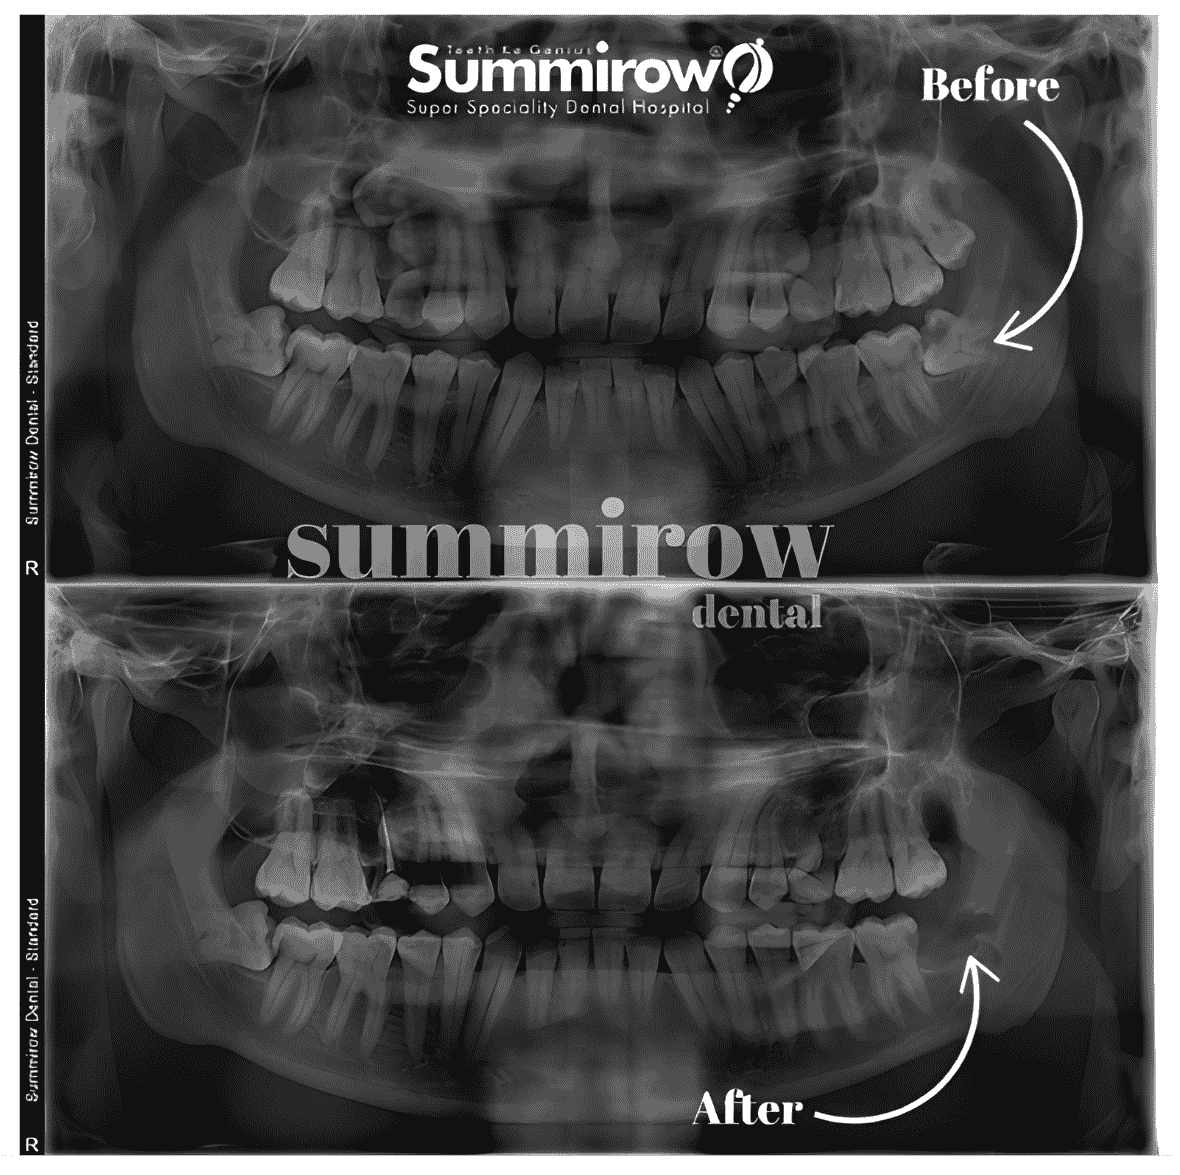

Choose wisely, See the Difference

wisdom-beforewisdom-after

Before

After